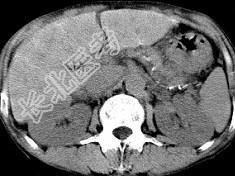

- 单项选择题男,40岁有血吸虫感染史, 腹胀不适,食欲减退, CT扫描所见如图,最可能的诊断是 ( )

A、肝炎后肝硬化

B、血吸虫后肝硬化

C、酒精性肝硬化

D、胆汁性肝硬化

E、脂肪肝